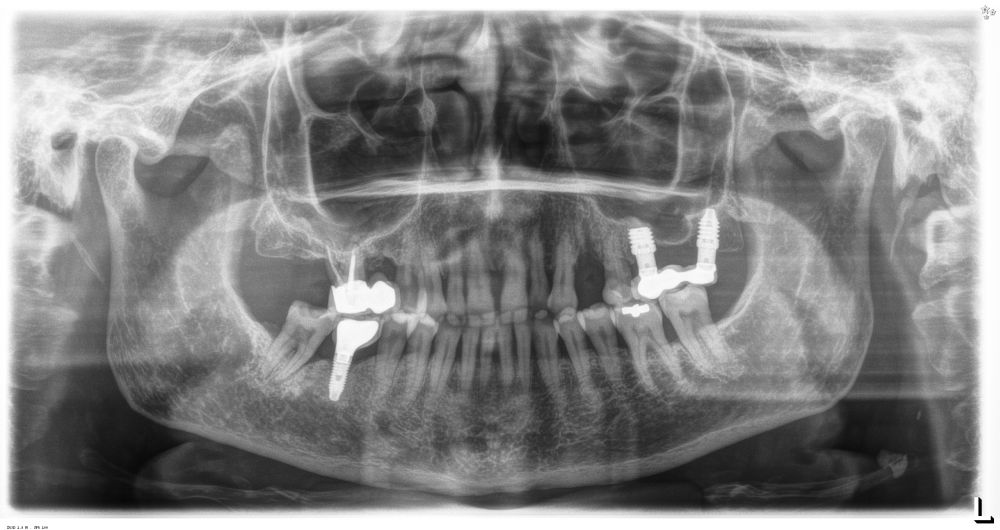

Métodos: Estudio prospectivo en 21 pacientes con implantes unitarios en molares/premolares de maxilar o mandíbula, seguidos durante tres años. Se recogieron datos clínicos y radiográficos cada seis meses. Se evaluaron: supervivencia implantaria, pérdida ósea marginal, presencia de mucositis o periimplantitis y complicaciones protésicas.

Fueron reclutados 21 pacientes en los que se colocaron 21 implantes que reunían los criterios de inclusión anteriormente descritos. Todos los implantes fueron de una longitud de 6,5 mm y el diámetro osciló entre los 3,50 mm el más frecuente con un 66,7% del total, hasta 3 mm en el 14,3%, siendo el restante 19% de diámetro de 3,3 mm. En cuanto a la disposición de los implantes, el 61,8% se situaron en la mandíbula siendo la posición más frecuente en localización de 45 y 46 con un 19% para cada localización. El 38,2% restante se situaron en el maxilar superior, siendo la localización más frecuente en las posiciones de 14 y 15 con un 9,5% cada una de ellas. El resto de las localizaciones se muestran en la Figura 1. El tipo óseo de los implantes insertados fue tipo II en el 66,7% de los casos, de tipo III en el 23,8% y de tipo I en el 9,5%. Si lo distribuimos por regiones anatómicas el más frecuente para el maxilar fue el tipo II (60%) y para la mandíbula también (54,5%). La distribución de los tipos óseos en función de la región se muestra en la Figura 2. El torque medio de inserción de los implantes fue de 37,14 Ncm (+/- 14,54). Los torques en función del tipo óseo y la localización anatómica se muestran en las Figuras 3 y 4. En 11 de los pacientes se llevó a cabo una carga inmediata, y en el resto una diferida.

En cuanto a la rehabilitación protésica, en todos los casos se utilizó una prótesis atornillada con transepitelial para prótesis unitaria. La supervivencia de las prótesis fue del 100%, sin encontrarse fracaso en ninguna de ellas al igual que los implantes, con un tiempo de seguimiento de tres años. Durante el primer año, en las visitas de control, ninguno de los implantes mostró sangrado al sondaje ni inflamación de los tejidos periimplantarios. La media de la pérdida ósea en este punto fue de 0,32 mm (+/- 0,60) y la media de la pérdida ósea distal de 0,31 (+/- 0,48). A los dos años, no se registraron tampoco signos inflamatorios en ninguno de los implantes y la pérdida ósea mesial del conjunto fue de media de 0,38 mm (+- 0,54) y la distal de 0,64 mm (+/- 0,70). En la última visita a los 3 años, los tejidos periimplantarios siguieron estables, sin signos de inflamación y la media de la pérdida ósea mesial fue de 0,40 mm (+/- 0,53) y la distal de 0,69 (+/- 0,55) (Figura 5). En las Figuras 6-12 se muestra uno de los casos incluidos en el estudio.